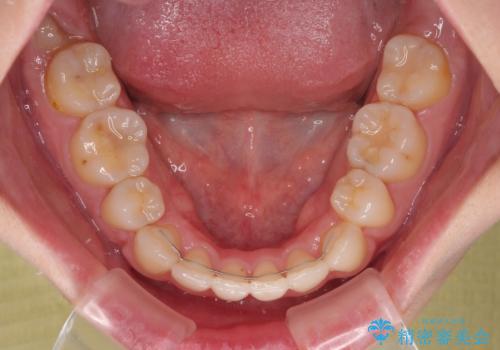

デコボコがスッキリするだけでなく、口元の突出感も少し改善され、満足のいく仕上がりとなりました。